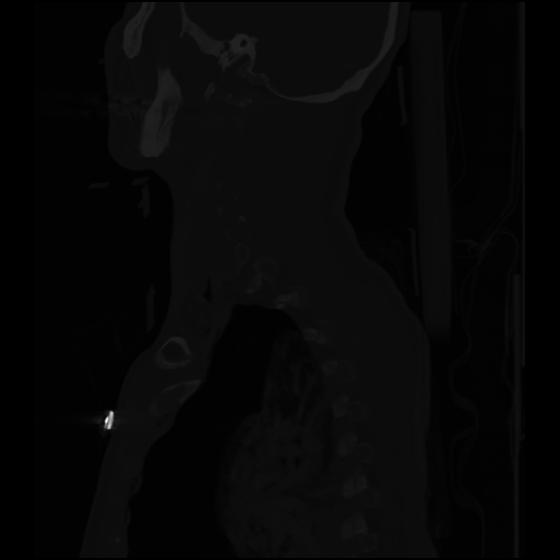

24 ANGIO,CE,Sag-MIP,5.000,ANGIO,Sag-MIP,